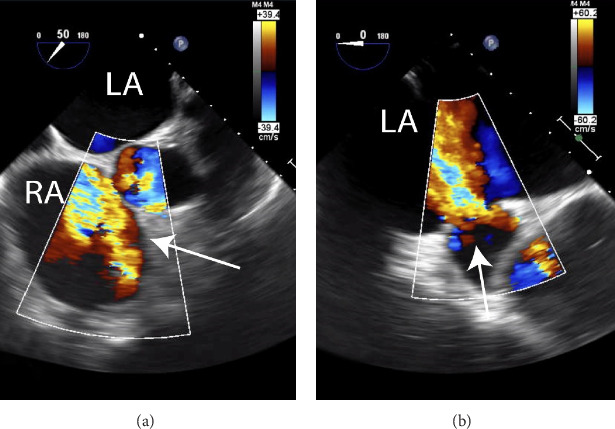

三尖瓣返流/破裂是一种罕见的创伤并发症,文献中仅报道了约150例,但由于临床表现微妙,这种发生率可能被低估。由于三尖瓣位于胸骨和椎骨之间的前解剖位置,它是钝性胸部外伤后最常受影响的心脏瓣膜。由于临床表现的微妙性,三尖瓣反流的诊断往往延迟在创伤设置。许多创伤患者也有分散性损伤。随后的治疗延误可能导致不可逆的右侧心室扩张,因此必须高度怀疑三尖瓣反流是胸部钝性创伤下急性血流动力学不稳定的原因。在这个报告中,我们提出了一个独特的病例外伤性三尖瓣反流的患者有先天性房间隔缺损(ASD)/部分异常肺静脉回流(PAPVR)的历史。

Tricuspid valve regurgitation/rupture is a rare complication of trauma, with only around 150 cases reported in the literature, though this prevalence may be underestimated due to subtle clinical manifestations. The tricuspid valve is the most frequently affected heart valve following blunt chest trauma due to its anterior anatomical position between the sternum and the vertebrae. The diagnosis of tricuspid regurgitation is often delayed in the traumatic setting due to the subtlety of clinical manifestations. Many trauma patients also present with distracting injuries. The subsequent treatment delay can result in development of irreversible dilatation of right-sided heart chambers, making it imperative to have a high index of suspicion for tricuspid regurgitation as a cause of acute hemodynamic instability in the setting of blunt trauma to the chest. In this report, we present a unique case of traumatic tricuspid valve regurgitation in a patient with a history of congenital atrial septal defect (ASD)/partial anomalous pulmonary venous return (PAPVR).